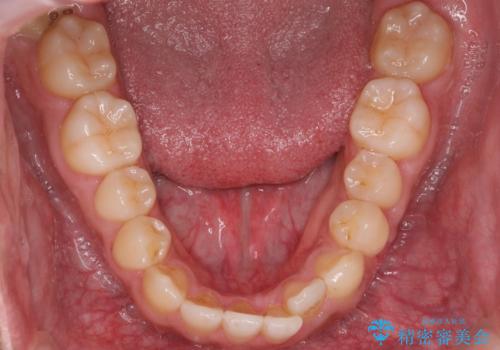

- 受け口を主訴に来院。

前歯のかみ合わせが逆になり上の前歯が奥に入っていました。

骨格性の受け口だったため、矯正用のミニスクリューを用いて、下の前歯をしっかり内側に入れました。

また、下顎はミニスクリューからマウスピースにゴムをかけて、下の歯並びが前に出ないようにして並べています。